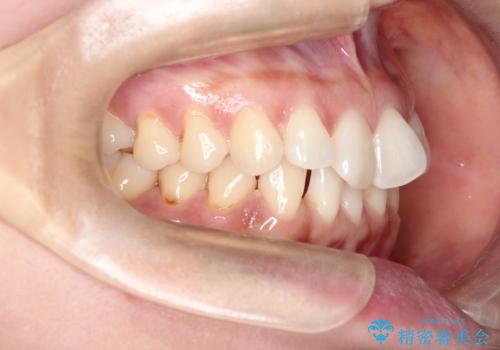

前歯のがたつきと隙間の矯正 インビザラインにて

- 上顎の前歯のがたつきと、下の前歯の隙間を主訴に来院されました。

下の前歯が先天的に欠損していました。

上顎の歯と歯の間をわずかに削りスペースを作り、ガタガタの改善し、下顎の前歯は隙間を閉じる計画としました。

非常に協力的な患者様でしたので、早期に治療が終了することができました。